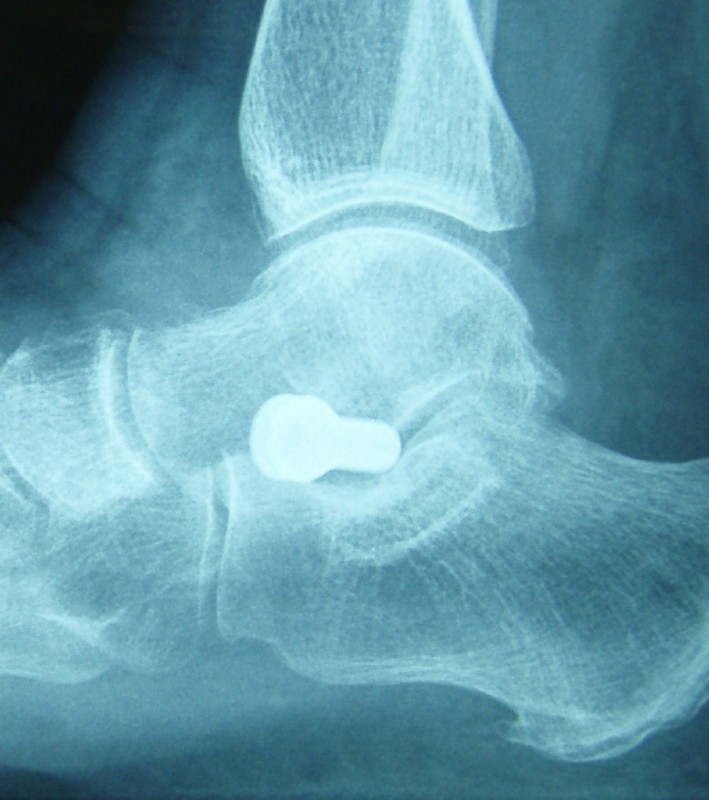

Das Implantat wird über einen 2 cm langen Schnitt minimal invasiv eingebaut. Das Röntgenbild zeigt das eingesetzte Implantat.

Das Implantat verhindert das Einknicken des Sprungbeines und damit auch das Einknicken des ganzen Fußes.

Es wird bei Kindern mit Beschwerden zwischen dem 6. und 12. Lebensjahr implantiert und lenkt das Wachstum des Fußes. Beim Erwachsenen mit noch flexiblem Knickplattfuß kann es ebenfalls verwendet werden. Es dient dann als "innere Korrektur" und spart dem Patienten eine deutlich größere Operation, wie sie beim Plattfuß zum Einsatz kommt.